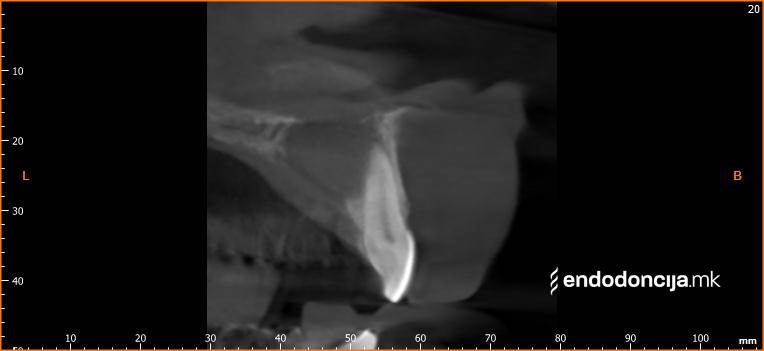

Στο Ειδικό Τμήμα Ενδοδοντικής, αντιμετωπίζουμε τους ασθενείς μας στο υψηλότερο επαγγελματικό και διαγνωστικό επίπεδο. Οι μονάδες θεραπείας μας είναι εξοπλισμένες με τα πιο σύγχρονα χειρουργικά μικροσκόπια, τα οποία υποστηρίζουν μια λεπτομερή αναπαράσταση και προετοιμασία ρίζας και προσφέρουν ένα εντελώς νέο επίπεδο ακρίβειας. Ο νεότερος ενδοδοντικός εξοπλισμός, όργανα και υλικά πλήρωσης χρησιμοποιούνται. Με αυτόν τον τρόπο μπορούμε να διατηρήσουμε τη θεραπεία όσο το δυνατόν συντομότερη, ακόμη και σε περίπλοκες περιπτώσεις, και να αποφύγουμε την απώλεια δοντιών.

Εκτός από την ανίχνευση των ριζικών καναλιών, η ενδελεχής προετοιμασία και η απολύμανση του ριζικού σωλήνα είναι η προϋπόθεση για μια επιτυχημένη συνολική θεραπεία. Μέσω της χρήσης των νεότερων οργάνων και αντιβακτηριακών διαλυμάτων, όλα τα υπολείμματα ιστών και τα βακτήρια που υπάρχουν μπορούν να εξαλειφθούν.

Οι υπηρεσίες του Ειδικού Τμήματος Ενδοδοντικής δεν περιορίζονται καθόλου στη συμβατική επεξεργασία ριζικών καναλιών. Αντιμετωπίζουμε αποκλειστικά τους ασθενείς μας με τα νεότερα υλικά και όργανα με μικροσκόπιο, προκειμένου να είμαστε σε θέση να καθαρίσουμε εντελώς και να προετοιμάσουμε όλα τα κανάλια πριν τα γεμίσουμε.